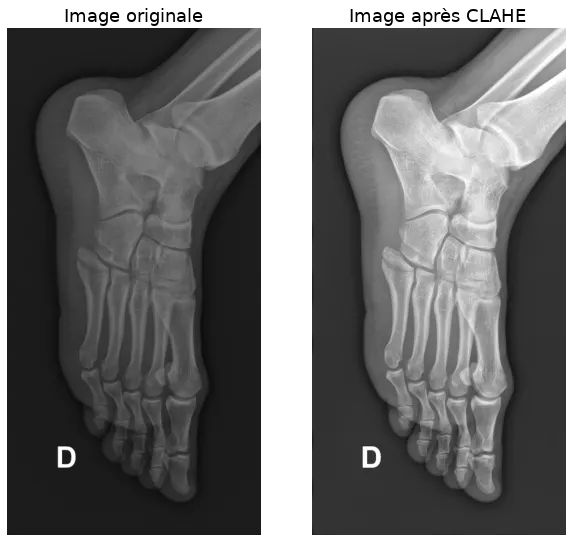

clahe CLAHE (contrast limited adaptive histogram equalization)

We also try to standardize the overall appearance of the images. Indeed, depending on the machines and their settings, the images may be more or less bright and contrasted. We use a preprocessing technique called CLAHE (contrast limited adaptive histogram equalization) to enhance contrast.